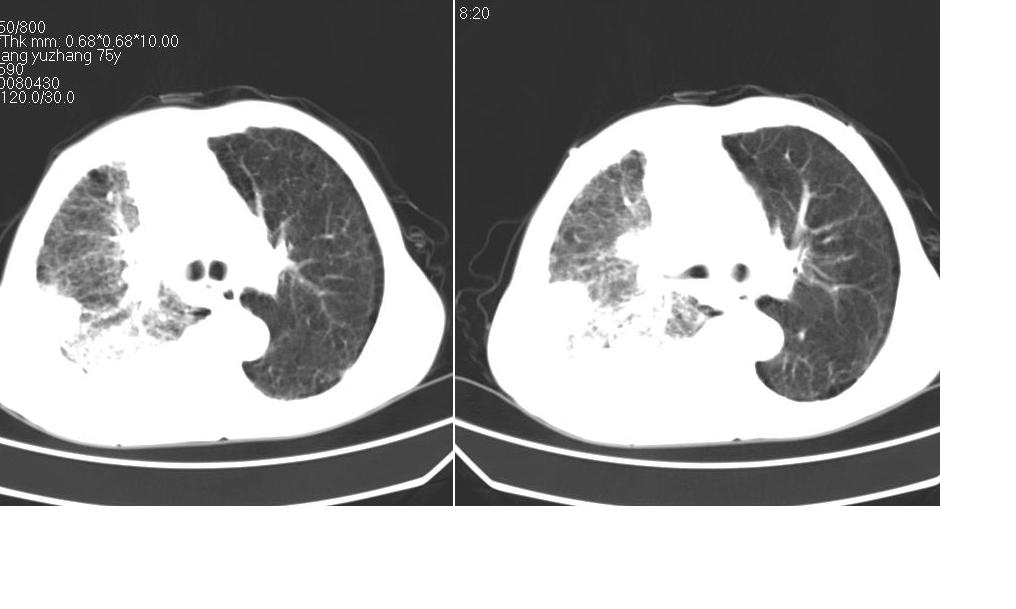

以下是引用zsl6918在2008-5-3 19:53:00的发言:[br]右肺中心型肺癌并纵隔淋巴结转移,胸膜转移,右肺癌性淋巴管炎。

以下是引用liuyue在2008-5-3 20:49:00的发言:[br]1.右侧中心型肺癌伴双肺转移瘤、纵隔淋巴结转移、右侧胸腔积液(侵及胸膜所致可能性大)。[br]2.右肺阻塞性肺炎,癌性淋巴管炎不除外。

以下是引用mzh123在2008-5-3 21:12:00的发言:[br]本人持有不同观点[br]1、右肺似有团块表现,但只有一个层面,所以本人认为还是以片为主,所以不能首先考虑肿瘤[br]2、右肺普遍成纤维化改变 并伴有片状炎症改变,和癌性淋巴管炎表现不同[br]3、所以本人认为是间质纤维化伴感染可能大 及胸腔积液